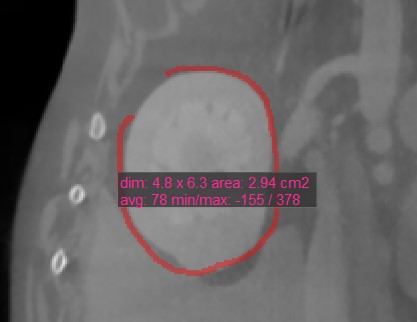

Polygon¶

Benutzer können mit dem Werkzeug Polygon

benutzerdefinierte, abgerundete Bereiche auf der aktiven Bildschicht erstellen, messen und markieren.

Wählen Sie das Werkzeug Polygon

aus und weisen Sie es einer der verfügbaren Maustasten zu. Starten Sie die Messung, indem Sie Punkte auf der aktiven Bildschicht setzen. Während der Benutzer die Punkte setzt, verbindet die Software sie automatisch und erstellt die abgerundete Form.

Schließen Sie die Messung, indem Sie den Pfad manuell schließen, oder doppelklicken Sie beim Setzen des letzten Punkts, um ihn automatisch zu schließen. Alle verfügbaren Messwerte werden zusammen mit der Messung angezeigt.

Ändern Sie den markierten Bereich, indem Sie einen der Punkte, die die Form beschreiben, mit dem Werkzeug Standard

verschieben.

Einige Messwerkzeuge im CT-Viewer werden verwendet, um einen Bereich auf der aktiven Bildschicht zu markieren. Es gibt vier Werte, die automatisch berechnet und zusammen mit diesen Messungen angezeigt werden.

Dim: Abmessungen der Messung (Breite, Höhe, Abstand)

Fläche: Die mit der Messung eingeschlossene Fläche, berechnet in Quadratzentimetern

Mittelwert: Der durchschnittliche Gewebedichtewert (HU), der durch die Messung erfasst wird. Höhere HU-Werte weisen auf dichteres Gewebe hin, wie z. B. Knochen.

Minimum/Maximum: Der Minimal- und Maximalwert geben den kleinsten und größten Gewebedichtewert an, der durch die Messung erfasst wird.